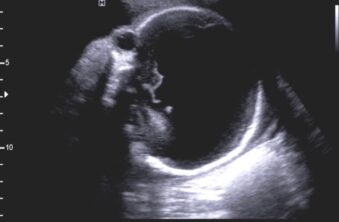

Holoprosencefalia alobar

Se caracteriza por marcados alteraciones en la línea media del encéfalo y/o malformaciones faciales.

Hallazgos radiológicos:

- Fusion completa de los hemisferios cerebrales

- Ausencia de la fisura interhemisferica y de la hoz cerebral

- Agenesia del cuerpo calloso y de la comisura anterior

- Holoventriculo, quiste dorsal

- Ausencia de septum pellucidum

- Los ganglios de la base de tálamos pueden estar diferenciados, funcionado o ausentes